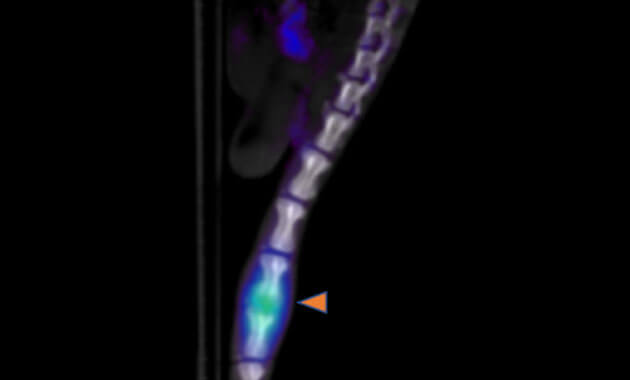

- Infection